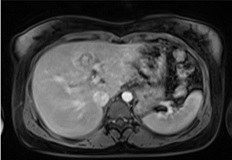

Hình ảnh siêu âm lại sau 12 tuần:

Hình 10, 11: Siêu âm lại sau 12 tuần: lớp nguyên bào nuôi bong ra làm khối thai trở nên hỗn hợp hơn. Vẫn còn tín hiệu mạch máu quanh khối thai.

Bệnh nhân sau khi được chẩn đoán được theo dõi Beta HCG mỗi tuần, không có bất kì can thiệp ngoại khoa hay sử dụng Methotrexate. Sau 12 tuần, Beta HCG của bệnh nhân giảm còn 234 mUI/ml